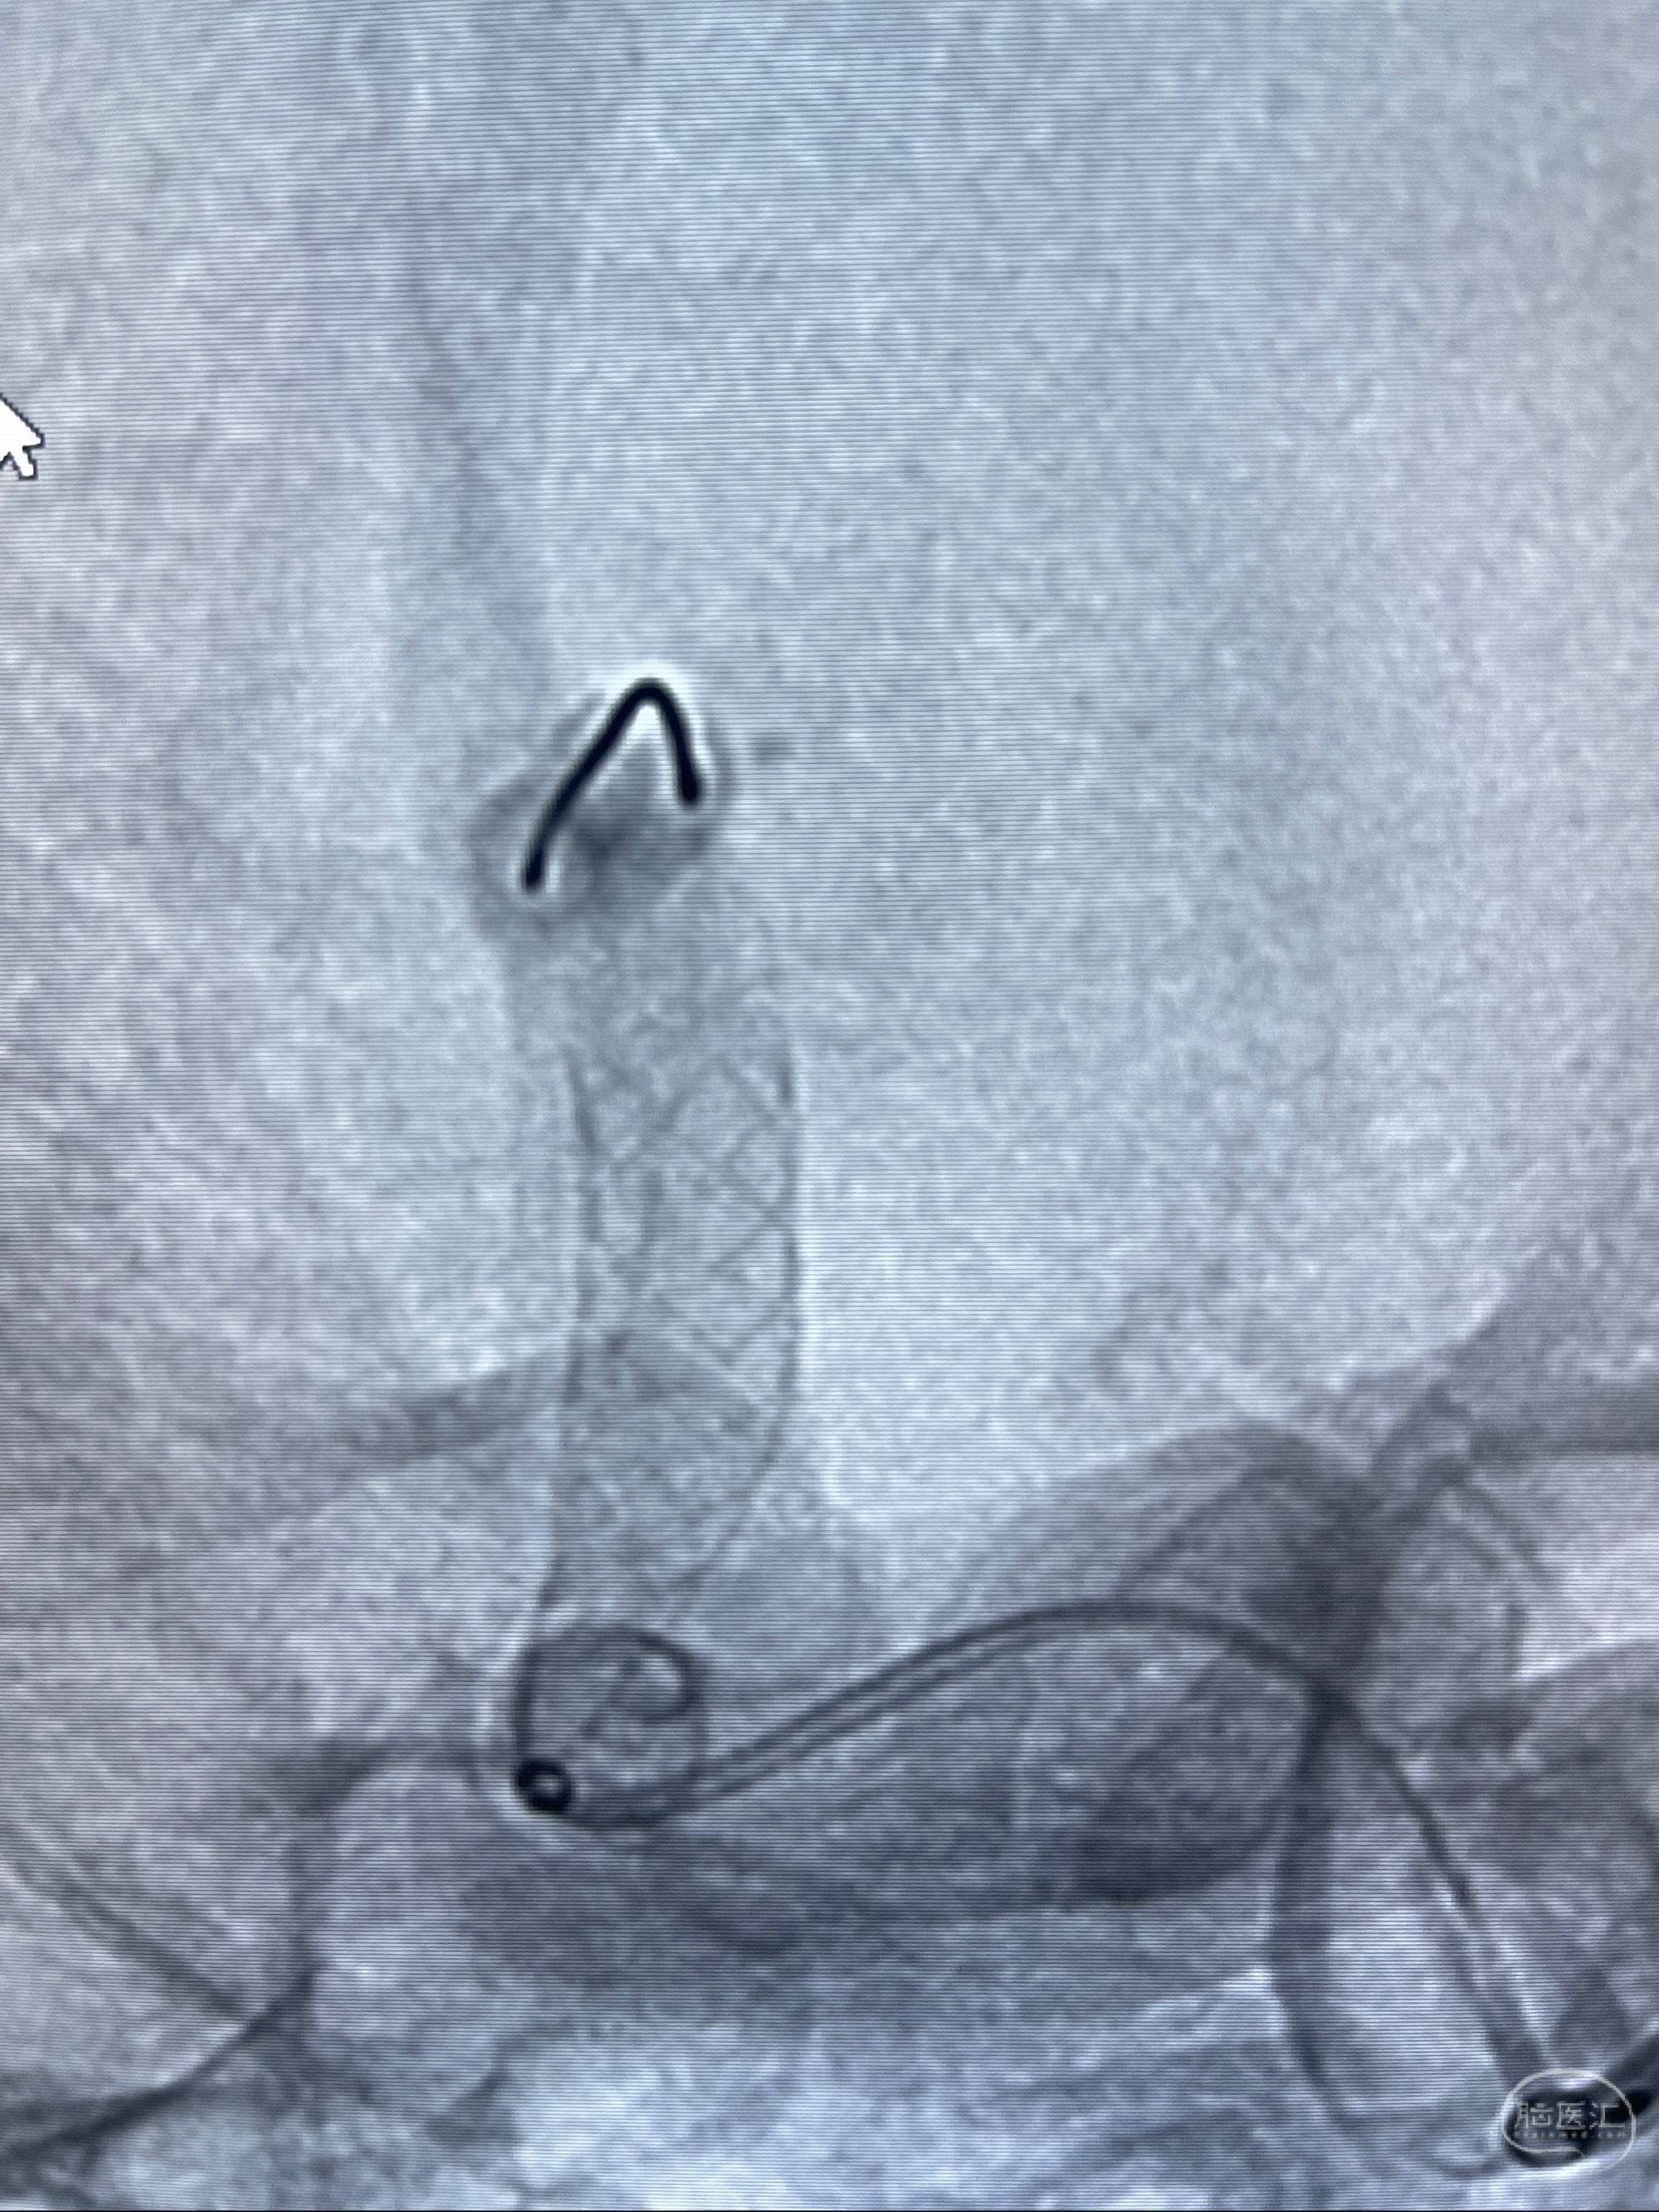

2023-07-27全脑血管造影:双侧颈内动脉眼动脉段动脉瘤,右侧较大

2023-08-01全麻下行双侧颈眼动脉瘤支架辅助栓塞

- pipeling4.5-20mm

- pipeline 4.0-20mm

手术顺利,麻醉苏醒佳,遵嘱动作